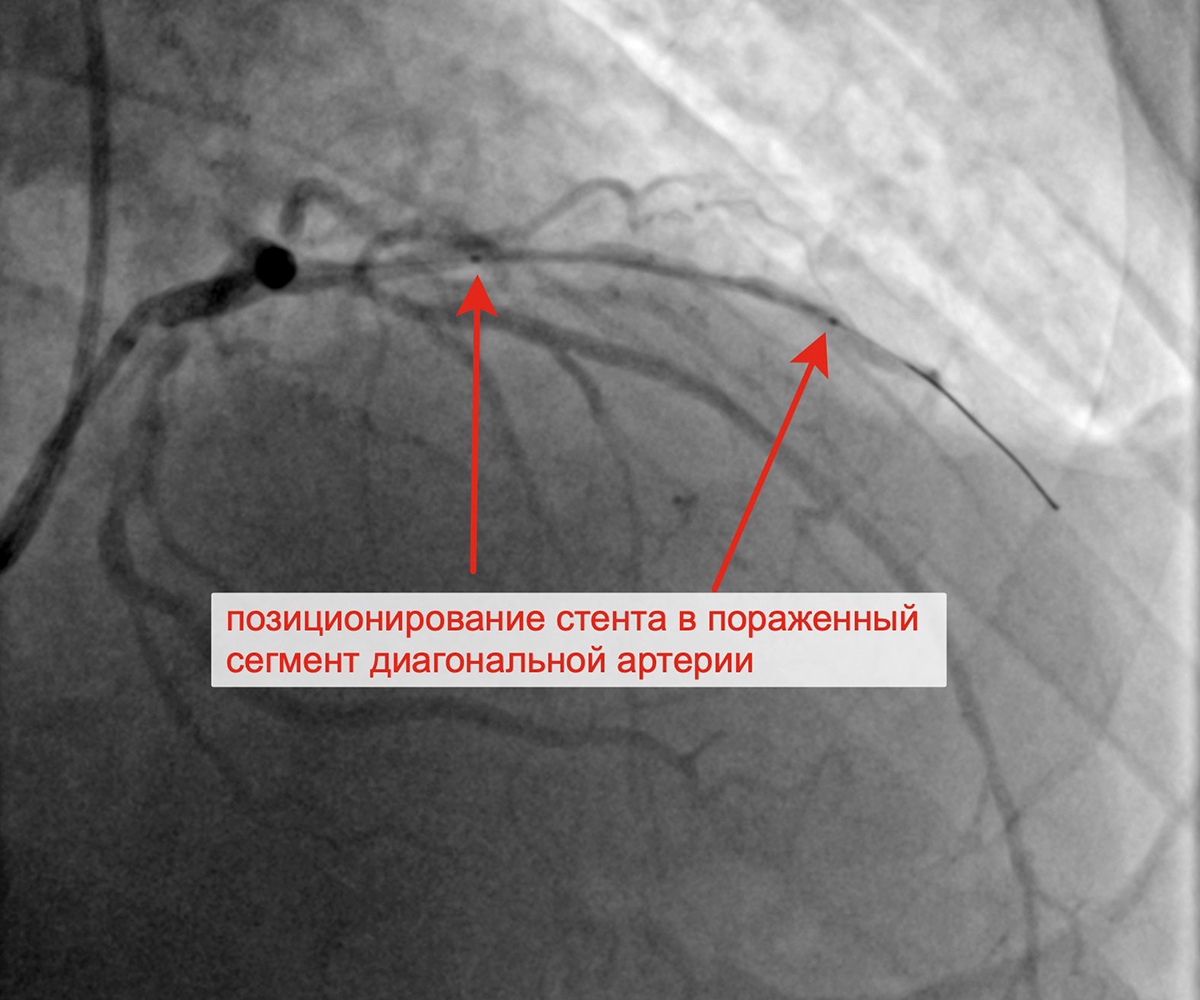

Вторым этапом в январе 2023 г. принято решение о проведении пациенту с персистирующей формой ФП, ГКМП, сохраняющейся клиникой стенокардии напряжения, известной коронарной анатомией, многососудистым поражением коронарного русла баллонной ангиопластики и стентирования крупной диагональной артерии (ДА) (1 стент с лекарственным покрытием). При контрольной ангиографии: стент и ДА проходимы, позиционирование стента адекватное, диссекции или остаточного стеноза в стентированном сегменте ДА нет, кровоток TIMI 3 по ДА и всем ее ветвям.

Стенозы диагональной артерии Выполнена баллонная ангиопластика ДА

Выполнено позиционирование и имплантация стента в ДА Финальный результат стентирования ДА